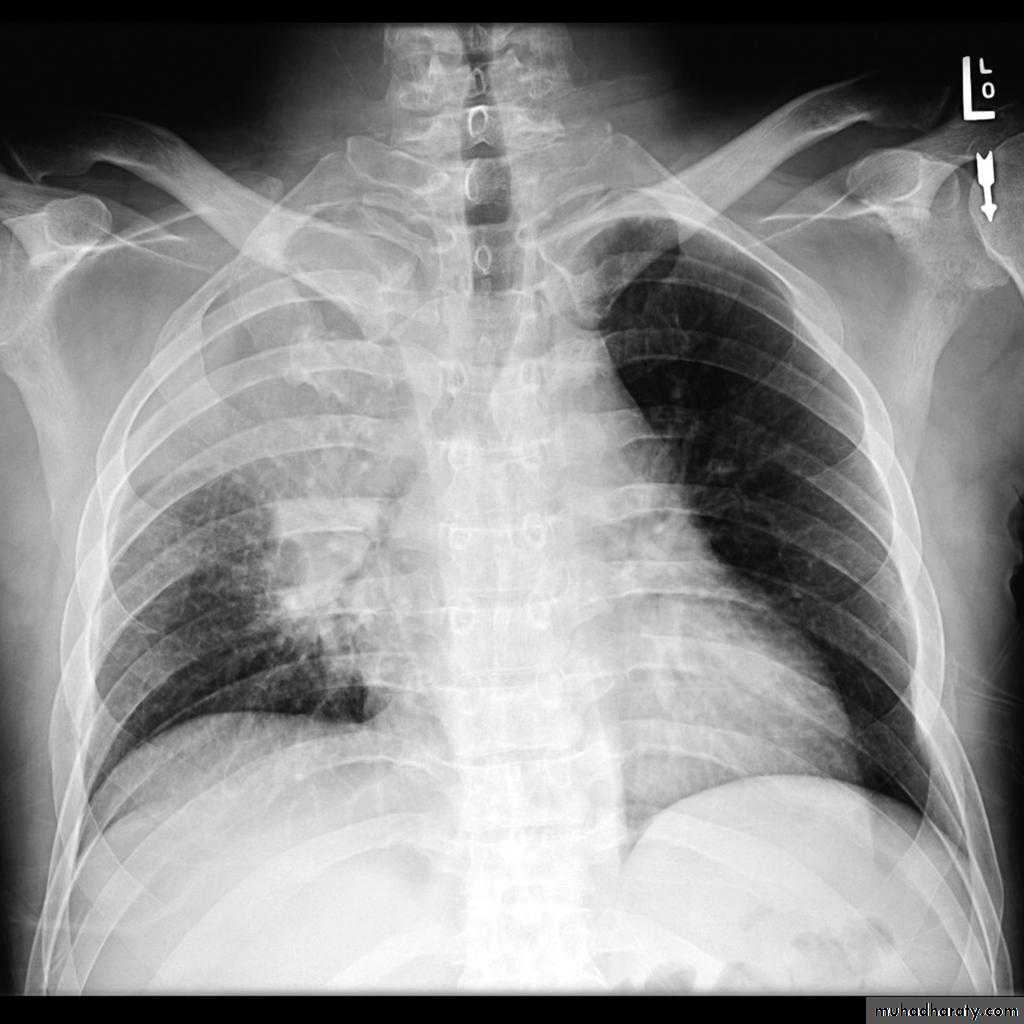

Bronchogenic CA

CT غير مطلوبbronchogenic carcinoma caused lung collapse

CXR of adult ,PA view shows:

Hilar mass +homogenus opacity in the upper right lobe with elevation of the horizontal fissure

Golden S sign

Shifting of the trachea to the same side